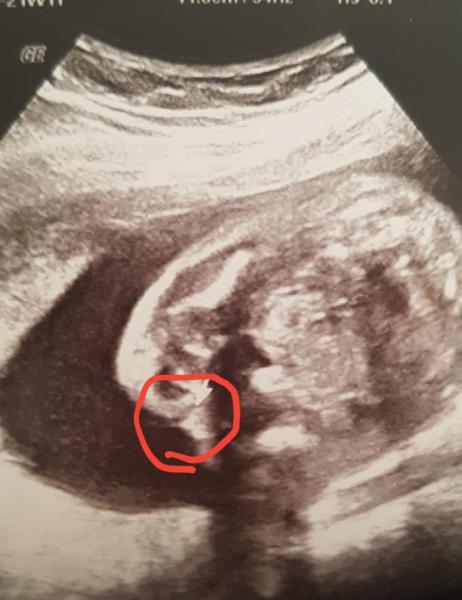

Huhu liebe Mädels, Wir kommen grad vom organscreening. Alles gut baby ist 25 cm und 430g schwer. Ich muss sagen, dass unsere Ärztin schon in der 12ssw. Geahnt hat, was es wird und sie wollte bei jedem Termin nur noch eine klare Bestätigung. Da dachte ich mir, möglicherweise ein junge, da sie es so früh erkennen konnte. So nun kugeln wir in der 22 SSW rum und zuerst meinte "aaaahh da hab ich was gesehen." mein Gedanke "alles klar, ein junge"... < 3 Dann schallt und schallt sie und meinte dann "ich habe vorhin eigentlich Hoden gesehen aber jetzt sieht es aus wie Schamlippen" Einen Schniedel haben wir leider nicht finden können. Nichts desto trotz möchte sie sich immer noch nicht festlegen. Was meint ihr? Es ist ein absolutes Wunschkind und nach drei Jahren und einem Verlust haben wir endlich ein kleines wunder im Anmarsch. Uns ist es egal ob Mädchen oder Junge. Aber ich möchte endlich wissen was es wird Vielleicht seht ihr was? Sie hat extra den Mauszeiger hinterlegt . aber ich kann beim besten willen nichts erkennen... Ich glaube wir haben einige Spezialisten in unserer Gruppe, die gerne mit raten dürfen

Bild zu Outing?? Wer mag spekulieren - Forum für August - Mamis

würde auf Schamlippen tippen da man nichts männliches dazwischen sieht und die Hoden dann sehr beieinander wären aber man weiß ja nie

Also bei dem was ich "erkenne" würde ich sagen, ein Mädchen

Ich meine, die Hoden sind bis zur Geburt noch in der Bauchhöhle, daher wird ich auf ne Prinzessin tippen.